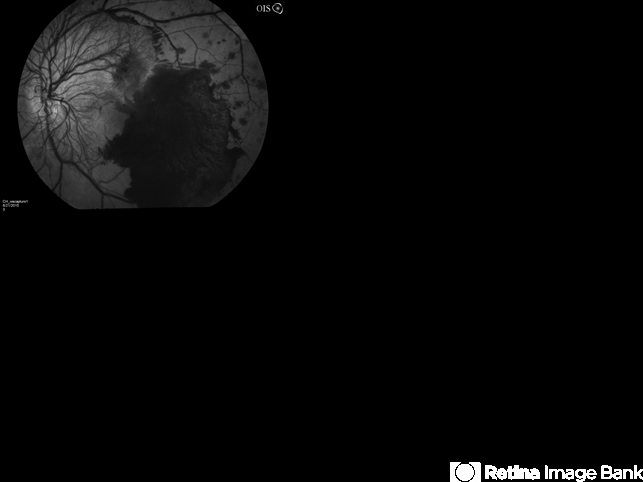

- proliferative diabetic retinopathy (PDR), retinal hemorrhage

- Proliferative diabetic retinopathy with neovascularization of the disc and a large retinal hemorrhage.